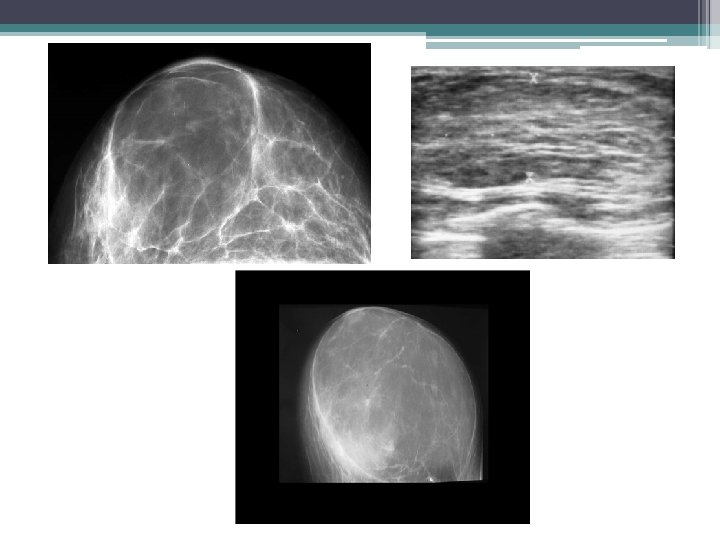

4. HAMARTOME • Tissu mammaire normal séparé du reste glande par pseudocapsule. • MAMMOGRAPHIE: aspect pathognomonique ▫ Formation bien limitée associant des plages radio opaques et radio transparents entourée d’une pseudo capsule(aspect de sein dans le sein) • ECHOGRAPHIE: ▫ Nodule bien limité ▫ Echostructure hétérogène ( hypo iso et hyper échogène) = tissu normal ▫ Pf s aucune traduction • IRM n’est pas indiquée

HAMARTOME